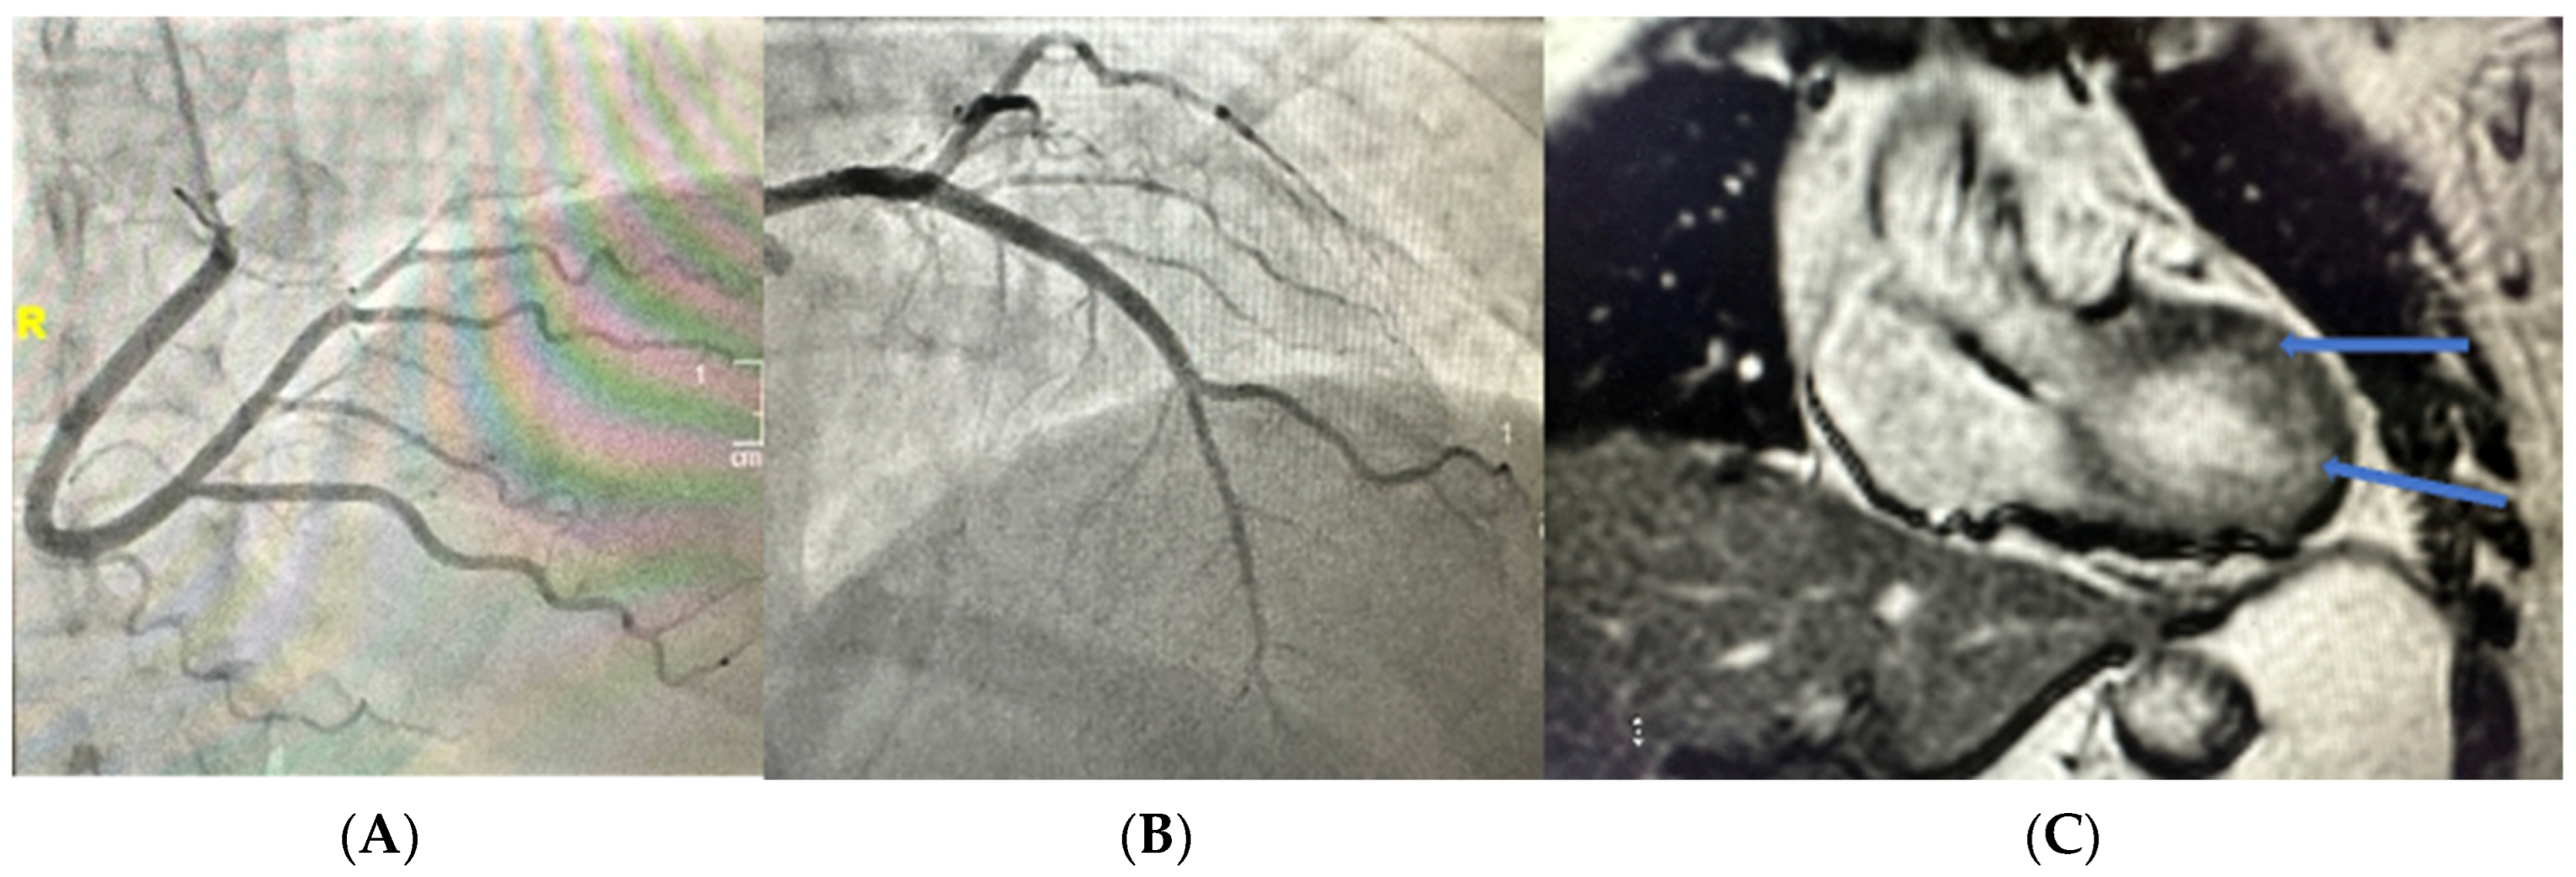

2. Clinical History